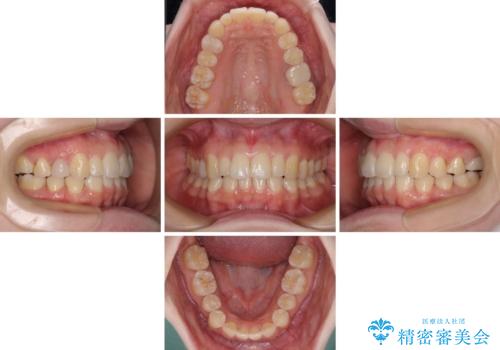

先天欠損のある歯列 インビザライン矯正

- 上顎前歯の突出感を気にして来院された患者様です。

下顎前歯2本が先天欠損しており、上顎歯列に対して、下顎歯列がアンバランスに小さい状況でした。

左右上顎側切歯2本が矮小歯であるため、上顎の抜歯ではなく、IPR(歯と歯の間を削る)と歯列全体の後方移動によってバランスを整えることとしました。

目立ちにくい装置を希望されたため、インビザラインにて治療を行うこととしました。